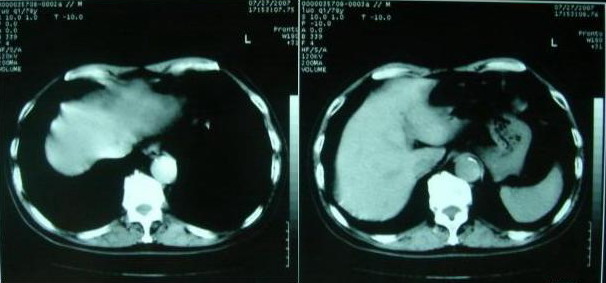

以下是引用zjzjr在2007-8-29 17:09:00的发言:[br]典型腹主动脉瘤累及双侧髂总动脉,建议增强扫描.

以下是引用why7912在2007-8-29 19:08:00的发言:[br]典型夹层动脉瘤,可见真假双腔及附壁血栓

以下是引用借我一双慧眼在2007-8-29 16:24:00的发言:[br]典型腹主动脉瘤累及双侧髂总动脉

以下是引用快乐男生在2007-8-29 16:45:00的发言:[br]腹主动脉及右髂总动脉大范围的管径增粗,[br]管壁多发的钙化,[br]并见真假腔(双腔征),假腔可见附壁血栓.[br]考虑腹主动脉夹层动脉瘤 .建议增强或mri